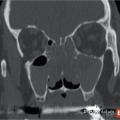

Polypose nasosinusienne

La polypose nasosinusienne est une rhinosinusite diffuse caractérisée par la présence de polypes bilatéraux dans les cavités nasales venant du massif ethmoïdal. Sa physiopathologie repose sur une inflammation chronique de la muqueuse des cavités nasales et sinusiennes marquée par une infiltration éosinophilique plus ou moins…